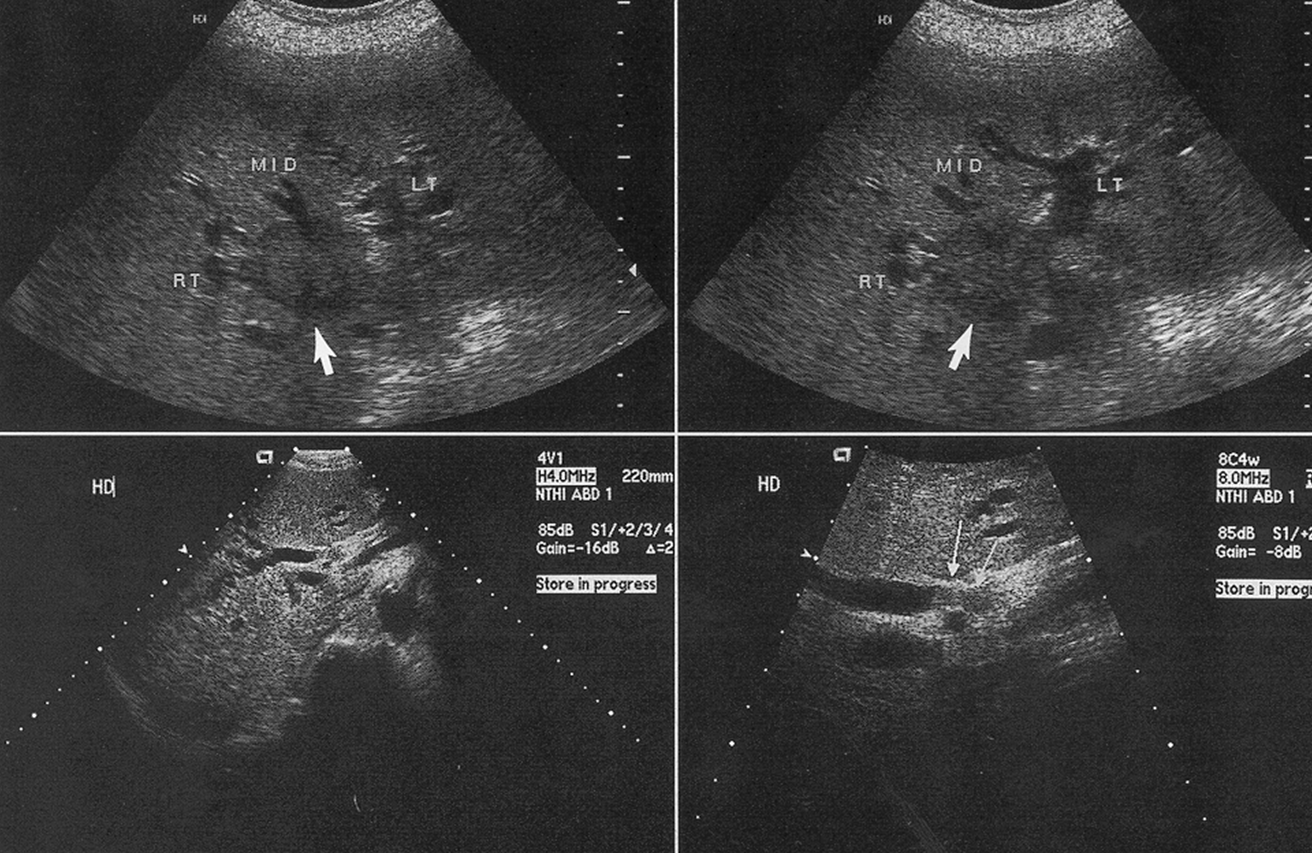

What is the arrow pointing to in the image above?

Hilar Cholangiocarcinoma/Klatskin’s Tumor

What are these images showing?

Klatskin’s Tumor